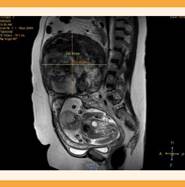

Se dispuso de una resonancia magnética nuclear para planeación quirúrgica en la que se encontró un leiomioma gigante subseroso, que emergía del fondo uterino, con datos de proceso degenerativo, de 350 x 180 x 172 mm, con compresión directa al útero gestante, las vísceras abdominales y la caja torácica. Se identificó otro leiomioma subseroso, con componente intramural hacia la cara lateral derecha de 105 x 80 mm de diámetro. El tercer leiomioma subseroso e intramural se ubicó en la cara anterior y el fondo uterino de 70 x 70 mm. Ninguna de las lesiones afectaba la inserción placentaria, pero los dos leiomiomas con componente intramural se observaron a 10 y 50 mm de la bolsa amniótica. Figuras 2y3

Figura 3 Resonancia magnética nuclear abdomino-pélvica, corte sagital, que muestra la disposición del leiomioma de mayor tamaño que evidencia la compresión sobre las asas intestinales, el útero, el feto y la vejiga.